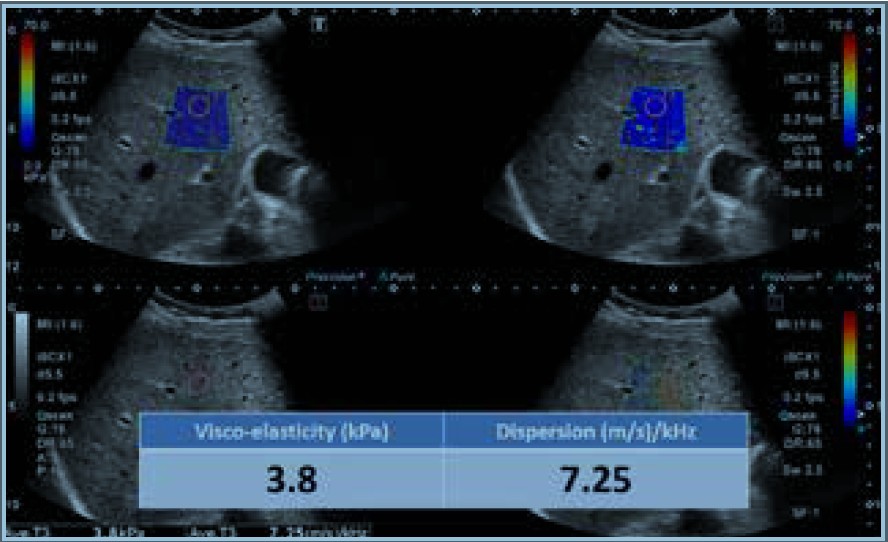

Малюнок 7. Випадок 1: Нормальна печінка

Тромбоцити: 309 × 103 мкл, AСT: 19 од/л, AЛT: 13 од/л, Загальний білірубін: 0,4 мг/дл

Випадок 1 (Малюнок 7) — це нормальна печінка, а випадок 2 (Малюнок 8) — печінка з НАСГ. НАСГ — це тип стеатозу, який демонструє гістологічні ознаки пошкодження гепатоцитів, включаючи гепатоцелюлярне балонування, часточкове запалення та/або фіброз печінки. Порівняно з нормальною печінкою НАСГ демонструє невелике збільшення еластичності, але залишається в межах норми. Проте спостерігається очевидне збільшення дисперсії.